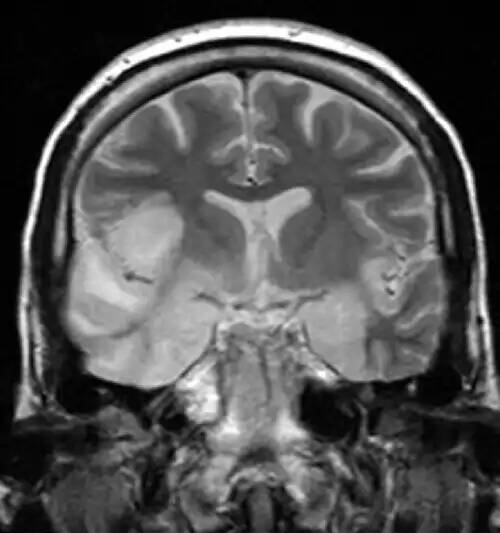

التهاب مغز یا انسفالیت ( به انگلیسی: Encephalitis ) به معنی التهاب حاد بافت مغزی است. شدت آن می تواند با علائمی از جمله کاهش یا تغییر در هوشیاری، سردرد، تب، گیجی، سفت شدن گردن و استفراغ متغیر باشد. عوارض ممکن است شامل تشنج، توهم، مشکل در صحبت کردن، مشکلات حافظه و مشکلات شنوایی باشد. علل آنسفالیت شامل ویروس هایی مانند ویروس هرپس سیمپلکس و ویروس هاری و همچنین باکتری ها، قارچ ها یا انگل ها است. علل دیگر عبارتند از بیماری های خود ایمنی و تأثیر برخی داروها. در بسیاری از موارد علت ناشناخته باقی مانده. عوامل خطر شامل دستگاه ایمنی ضعیف می باشد. تشخیص معمولاً بر اساس علائم است و با آزمایش خون، تصویربرداری پزشکی و تجزیه و تحلیل مایع مغزی نخاعی پشتیبانی می شود. انواع خاصی از آن با واکسن ها قابل پیشگیری هستند. درمان ممکن است شامل داروهای ضد ویروسی ( مانند آسیکلوویر )، داروهای ضد تشنج و کورتیکواستروئیدها باشد. درمان به طور کلی در بیمارستان انجام می شود. برخی افراد نیاز به تنفس مصنوعی خواهند داشت. پس از اینکه مشکل فوری فرد مورد کنترل قرار گرفت، ممکن است نیاز به توانبخشی باشد. در سال ۲۰۱۵ میلادی تخمین زده شد که آنسفالیت ۴٫۳ میلیون نفر را تحت تأثیر قرار داده و منجر به مرگ ۱۵۰۰۰۰ نفر در سراسر جهان شده است.